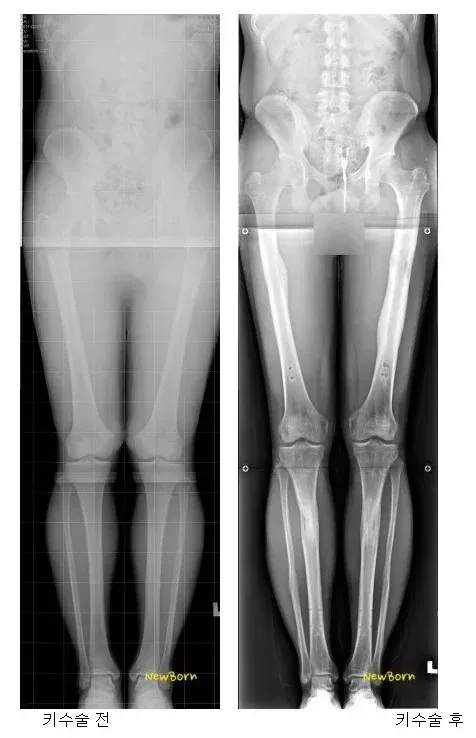

인생걸고 받을 만큼 키 스트레스가 엄청 났을듯 고생한 만큼 좋은 일만 가득하길 장기 별 최악의 음식 정리1000km 5분 완충 신의 배터리 양산갓 전역한 20대 남자가 600만원으로 독립하는 법한국은 상속세 때문에 대형 카페 천국이 된 듯신기하게 생긴 희귀종 콩들